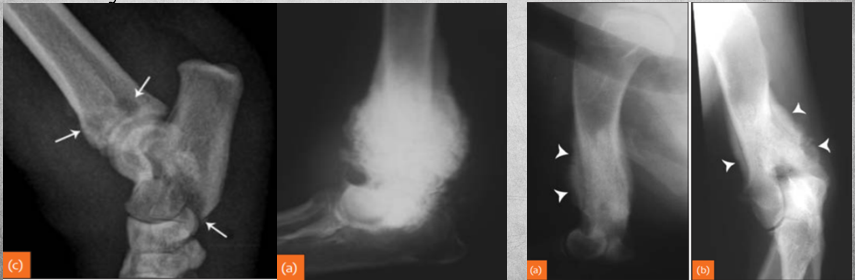

What does this depict?

Premature closure of growth plate distal radius.

Describe Premature closure of growth plate.

e.g. distal ulna such as in image

results in growth discrepancy and may disrupt the function of the joint